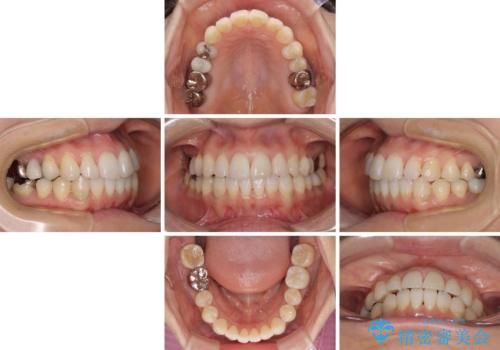

インビザライン・ライトによる矯正治療であったので、時間をかけずに治療を終えることができました。

口を開ける度に目立っていた銀歯もセラミックで自然な口元の印象となりました。